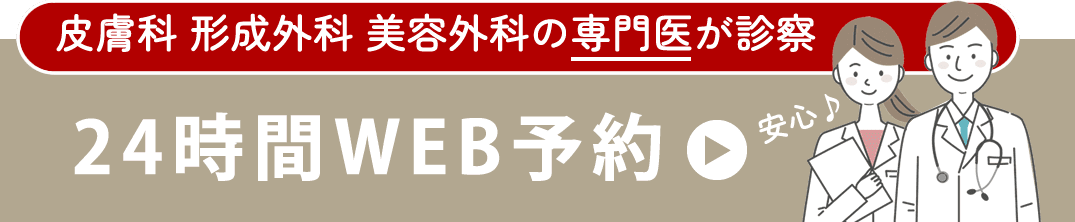

術前のマブタ。目を凝らして見ても、埋没の結び目は分かりません。 ”今ある二重ライン上に結び目があるんだろうな” と推測して手術を行いました。